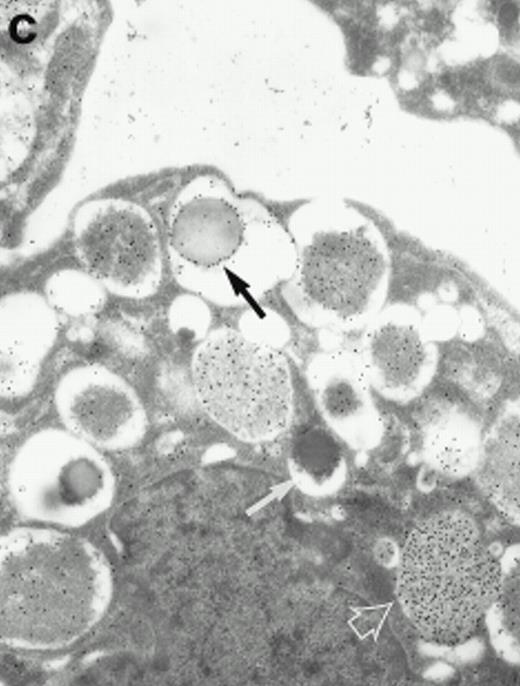

Morphologic analyses of both mature eosinophils and day-24 IL-5–induced UCC by immunoelectron microscopy were performed with proMBP-specific monoclonal antibody (J163-15E10) and with polyclonal antibody to MBP (rabbit #14). No proMBP staining was observed in peripheral blood eosinophils (Fig 6a); in contrast, MBP was localized specifically to the granule crystalline core (Fig 6b). Day-24 IL-5–induced UCC showed marked proMBP labeling of large uncondensed granules and minimal labeling of small condensed granules (Fig 6c); remarkably, proMBP was often seen as a ring around what appeared to be a granule in the process of condensing (black arrow). MBP labeling was confined primarily to condensing granules (Fig6d). Figure 7 shows results from double immunogold labeling of both proMBP (small gold) and MBP (large gold). ProMBP was concentrated in large uncondensed granules, and MBP was concentrated in condensed granules. Some granules (black arrow in Fig7b) contained labeling for MBP (primarily in the center) and proMBP (at the periphery). Controls using either normal mouse immunoglobulin or normal rabbit immunoglobulin as the primary label were negative (results not shown).

Localization of proMBP and MBP by immunoelectron microscopy. (a) A peripheral blood eosinophil labeled with anti-proMBP J163-15E10. Note the absence of specific labeling. (b) A peripheral blood eosinophil labeled with rabbit anti-MBP. Note that MBP is specifically localized to the granule crystalline core (black arrows). (c) Day-24 IL-5–induced UCC labeled with anti-proMBP. The black arrow shows localization of proMBP predominantly to the periphery of a condensing granule; very little proMBP is present in the interior of that granule. The white arrow points to a condensed granule, which lacks proMBP label. Also, note the presence of a large uncondensed granule densely labeled with proMBP proximal to the nucleus (open white arrowhead). (d) Day-24 IL-5–induced UCC labeled with anti-MBP. MBP is localized primarily to the interior of condensing granules (black arrows). (a, c, and d) Original magnification ×11,000; (b) ×15,000.